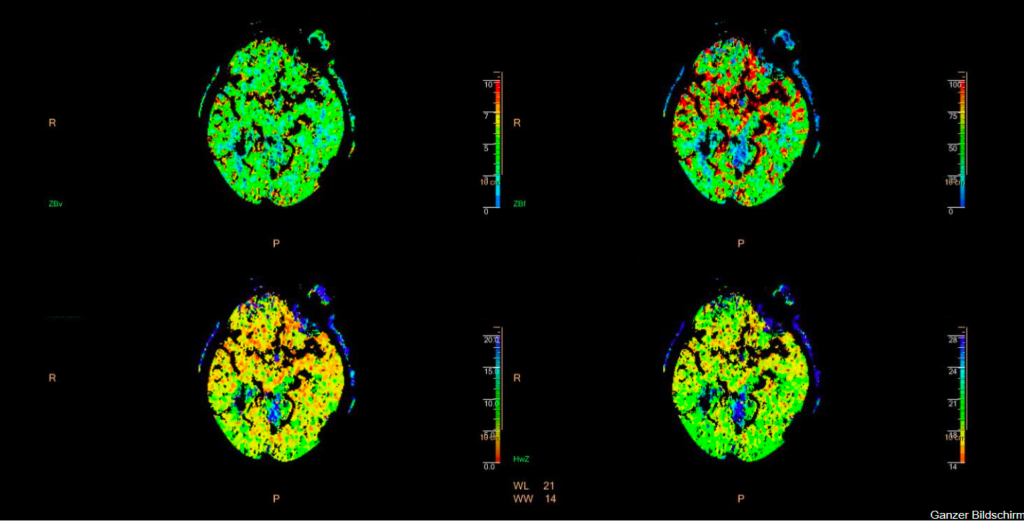

Typischerweise werden 40 ml Röntgen-Kontrastmittel mit relativ hoher Infusionsgeschwindigkeit (5 ml/s) infundiert. Dann wird durch repetitive CT-Messungen das An- und Abfluten des Kontrastmittels im Kopf gemessen, was über den Anstieg der Hounsfield Unit-Werte ja sogar quantifiziert werden kann. Dies macht man in den Arterien, den Venen und im Parenchym. Es entstehen bei den üblichen Protokollen ca. 30 CT-Aufnahmen hintereinander, welche alle 2 Sekunden angefertigt werden, so dass eine CT-Perfusionsmessung in der Regel ziemlich genau eine Minute dauert. Es gibt allerdings auch andere Protokolle und bei einer schlechten Pumpfunktion des Herzens ist das (so zeigt es auch die klinische Erfahrung) auch gar nicht so selten zu kurz. 30 CT-Aufnahmen hintereinander verursachen eine nicht unerhebliche Strahlenbelastung, auch wenn die Dosis pro CT-Messung schon reduziert wird (was man auch an der Bildqualität der CT-Perfusionsmessungs-Bilder sehen kann). Es entstehen dann zwei Messparameter (und das sind auch die entscheidenden, die anderen beiden kann man für die meisten Fälle erst einmal in den Skat drücken). Das sind die mittlere Transitzeit oder mean transit time oder MTT und das ist das zerebrale Blutvolumen oder cerebral blood volume oder CBV. Die MTT beschreibt die Zeit, die das Kontrastmittel zum An- und Abfluten im Hirngewebe braucht und ist am Ende eine Korrelation aus der Messkurve aus der Arterie und des Hirngewebe selber. Die CBV ist so ein schöner area under the curve-Messwert und vergleicht KM-Aufnahme im Hirnparenchym (unter der Kurve des An- und Abflutens) mit dem An- und Abfluten in den Venen (und hier auch als Fläche unter der Kurve). Die Idee ist dann, dass die CBV angibt, wo überhaupt noch Kontrastmittel hinkommt (eben nicht in den Infarktkern) und die MTT, wo das Kontrastmittel langsamer an- und abflutet, nämlich im Risikogewebe. Dazu kommt, dass im Risikogewebe durch die Weitstellung aller Kollateralgefäße das CBV meistens normal bis erhöht ist. Die beiden anderen – eher nicht so entscheidenden – Parameter sind dann noch die Halbwertszeit oder time to peak oder TTP, was einfach die halbe MTT bis zum Scheitelpunkt ist und der zerebrale Blutfluss oder CBF, was der Quotient aus CBV und MTT ist. Dies bedeutet, dass man – nach der Idee hinter der CT-Perfusionsbildgebung – dann in der CBV den Infarktkern und in der MTT die Penumbra sehen würde und kleiner Infarktkern und große Penumbra dann unsere Mismatch-Analogie darstellen würde.

Für den anspruchsvollen Connaisseur sei noch erwähnt, dass die TTP in erster Linie im CT-Protokoll auftaucht, weil sie in der MRT-Perfusionsbildgebung relativ viel benutzt wird und dass das ganze (die MRT-Perfusion noch mehr, das werden die Freunde der CT-Perfusion auch nicht müde zu betonen), daran krankt, dass es keine allgemein akzeptierten und standardisierten Messwert-Grenzen gibt, da das Ergebnis der Perfusionsbilder relativ stark vom Gerät, seinen Einstellungen, der Software, dem Hersteller, dem Patienten und seiner kardinalen Pumpfunktion usw. abhängt. Das führt dann oft zu solchen Aussagen wie: “Aber hinten links ist es doch irgendwie ein bisschen blauer in der MTT“. Ganz grob konnte man sich darauf einigen, dass eine MTT von 4-6 Sekunden normal ist und dass eine Verdoppelung der MTT (und/oder der TTP) für eine signifikant schlechtere Perfusion spricht. Für den CBF gibt es sogar eine Dreiteilung: > 50 ml/100 g Hirngewebe ist normal, bei < 20 ml/100 g Hirngewebe liegt eine ischämische Situation vor und unter 10 ml/100 g Hirngewebe eine strukturelle Infarzierung. Beim CBV muss man wissen, dass im Kortex typischerweise mehr Blut ist als im Marklager (was auch irgendwie nicht verwundert), da geht man physiologischerweise von 5-6 ml/100 g Hirngewebe im Kortex und von 2-3 ml/100 g Hirngewebe im Marklager aus. Bei einem kortikalen CBV von weniger als 2 ml kann man einen Infarktkern annehmen. In der hinteren Strombahn, in der ja langsamere Flussgeschwindigkeiten vorherrschen, sind vor allem die MTT- und TTP-Werte deutlich länger.